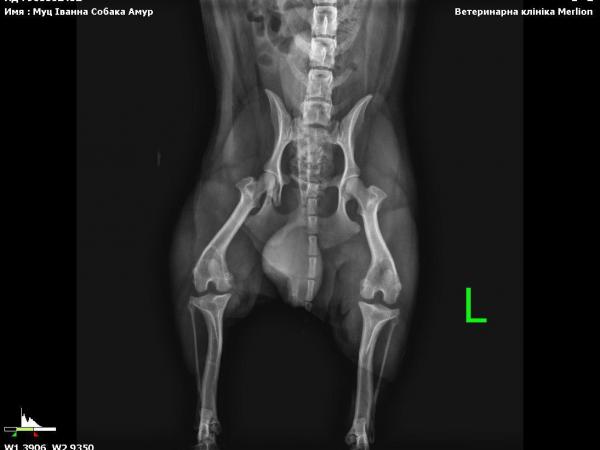

In der Klinik stellte sich heraus, dass Gucio etwa 3 Jahre alt ist und eine gebrochene Beckenregion hat. Wahrscheinlich wurde er von einem Auto angefahren. Deshalb konnte er sich nicht bewegen und lag an einer stark befahrenen Straße — ohne jede Chance, wenn niemand angehalten hätte.

Er erhielt erste tierärztliche Hilfe — Untersuchung, Impfung, Entwurmung. Sein Zustand wurde als schwer eingestuft: starke Unterkühlung, Erschöpfung und eine Verletzung, die eine langfristige Behandlung und Rehabilitation erfordert.